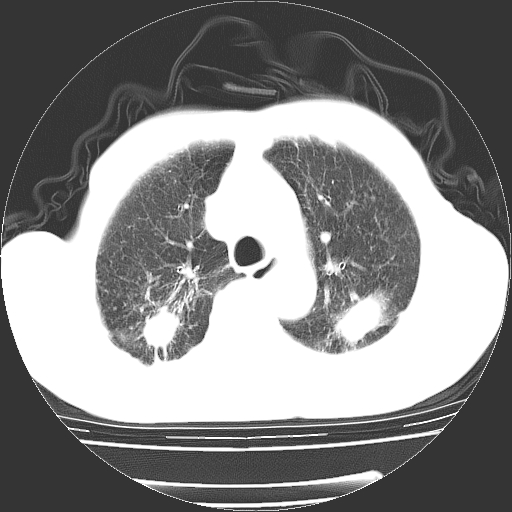

男,72岁,反复咳嗽、憋气一年余,有15年的煤矿井下工作史。

两上肺为主的大小不等结节影伴广泛纤维化,结合病史考虑尘肺。

1、双肺中上叶结节影结合病史考虑巨块型矽肺结节。

2、慢支炎并肺气肿

3、双下肺纤维化灶并左下肺局限性肺气肿。

支持 尘肺,肺心病?-------15年的煤矿井下工作史,双上肺叫对称的片团结节影,内见斑状钙化,边缘见粗长毛刺影,肺纹理混乱,可见网状及磨玻璃样影,肺门纵膈见多个淋巴结钙化